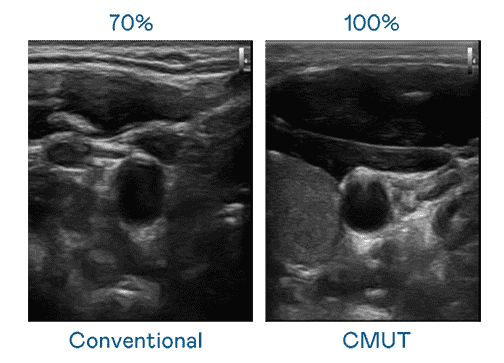

CMUT 技术是一种用电容式微机电元件来产生超音波讯号的技术。。。与传统 PZT 压电式技术相比,,,CMUT 频宽增加 30%,,更宽频的超音波讯号让影像解析度大幅提升,,是实现高影像品质医疗超音波扫描、、促进精准医疗发展的关键技术。。

大频宽带来超清晰影像

超音波影像的解析度高低,,首先取决于探头能发出的讯号频宽。。。开云电子 CMUT 可提供高清晰的超音波讯号,,,,提供高频宽、、、高灵敏度、、、影像纹理细节更高的超音波影像,,,协助医护人员缩短影像判读时间及利用精准的医疗影像进行诊断。。。。